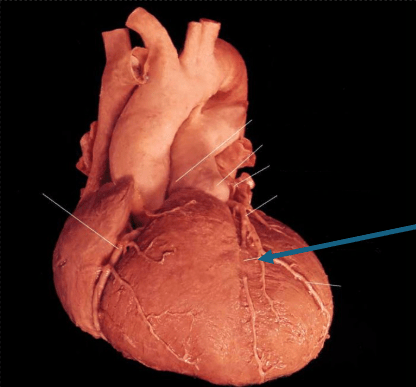

The most common surgically significant coronary anomaly seenhere in Tetralogy of Fallot patients, occurring in 4-7% of patients.

What is anomalous origin of the LAD from the RCA? The course of ther artery puts it at risk during standard ventriculotomy, as the LAD crosses over the RVOT.